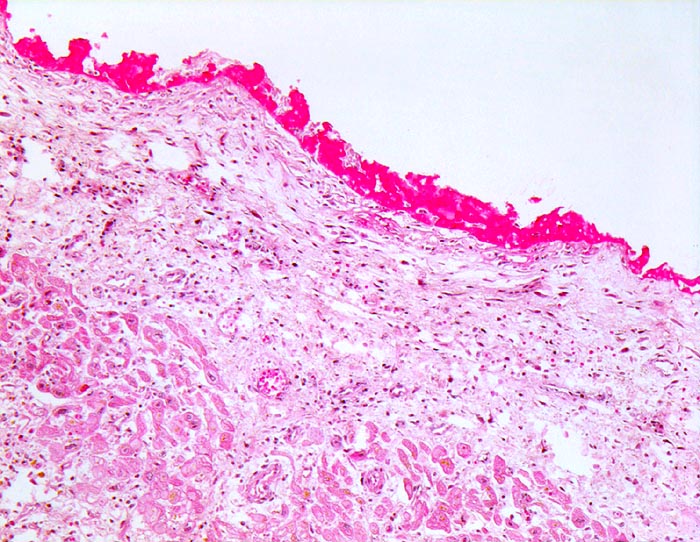

PathoPic ID 4541 - Pericarditis fibrinosa episthenocardiaca

Pericarditis fibrinosa episthenocardiaca

Entzündung / Reparatur

Perikard

Körperhöhlen, Serosa

Epikard mit zottigen

Fibrinauflagerungen.

Diagnose eines Myokardinfarktes vor 8 Tagen.

Histologie

50